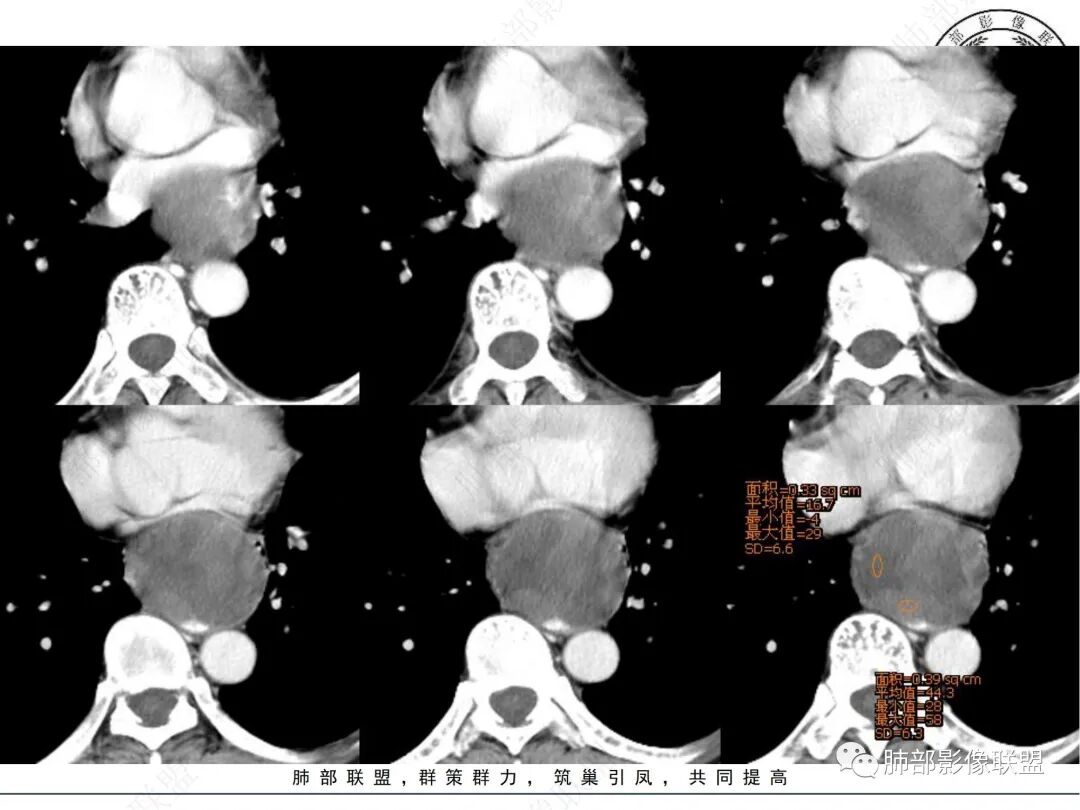

临床:中老年男性,体检发现后纵隔占位,

影像表现:后纵隔类圆形软组织肿块,增强扫描不均匀强化,内部可见囊变区及实性区,实性区明显延迟强化,边界清晰,邻近左心房及食管受压改变,

定位定性:后纵隔良性肿瘤,

诊断:神经源性肿瘤,神经鞘瘤

鉴别诊断:1.sft,2.CD,边缘似乎有钙化,3.血管源性肿瘤,部分区域明显延迟强化

1. 中老年男性,偶然发现后纵隔占位(没有吞咽梗阻等消化道症状)。实验室检查无特殊。

2. 后纵隔类圆形囊实性占位,整体圆张力大,边界光整,增强后不均匀强化(似乎形成AB区?),轻度强化囊性区明显强化实性区,病灶边缘有明显强化血管影,与食道前壁界限不清,且食道明显受压,主动脉血管受压有脂肪间隙。考虑神经源性肿瘤,神经鞘瘤的可能。